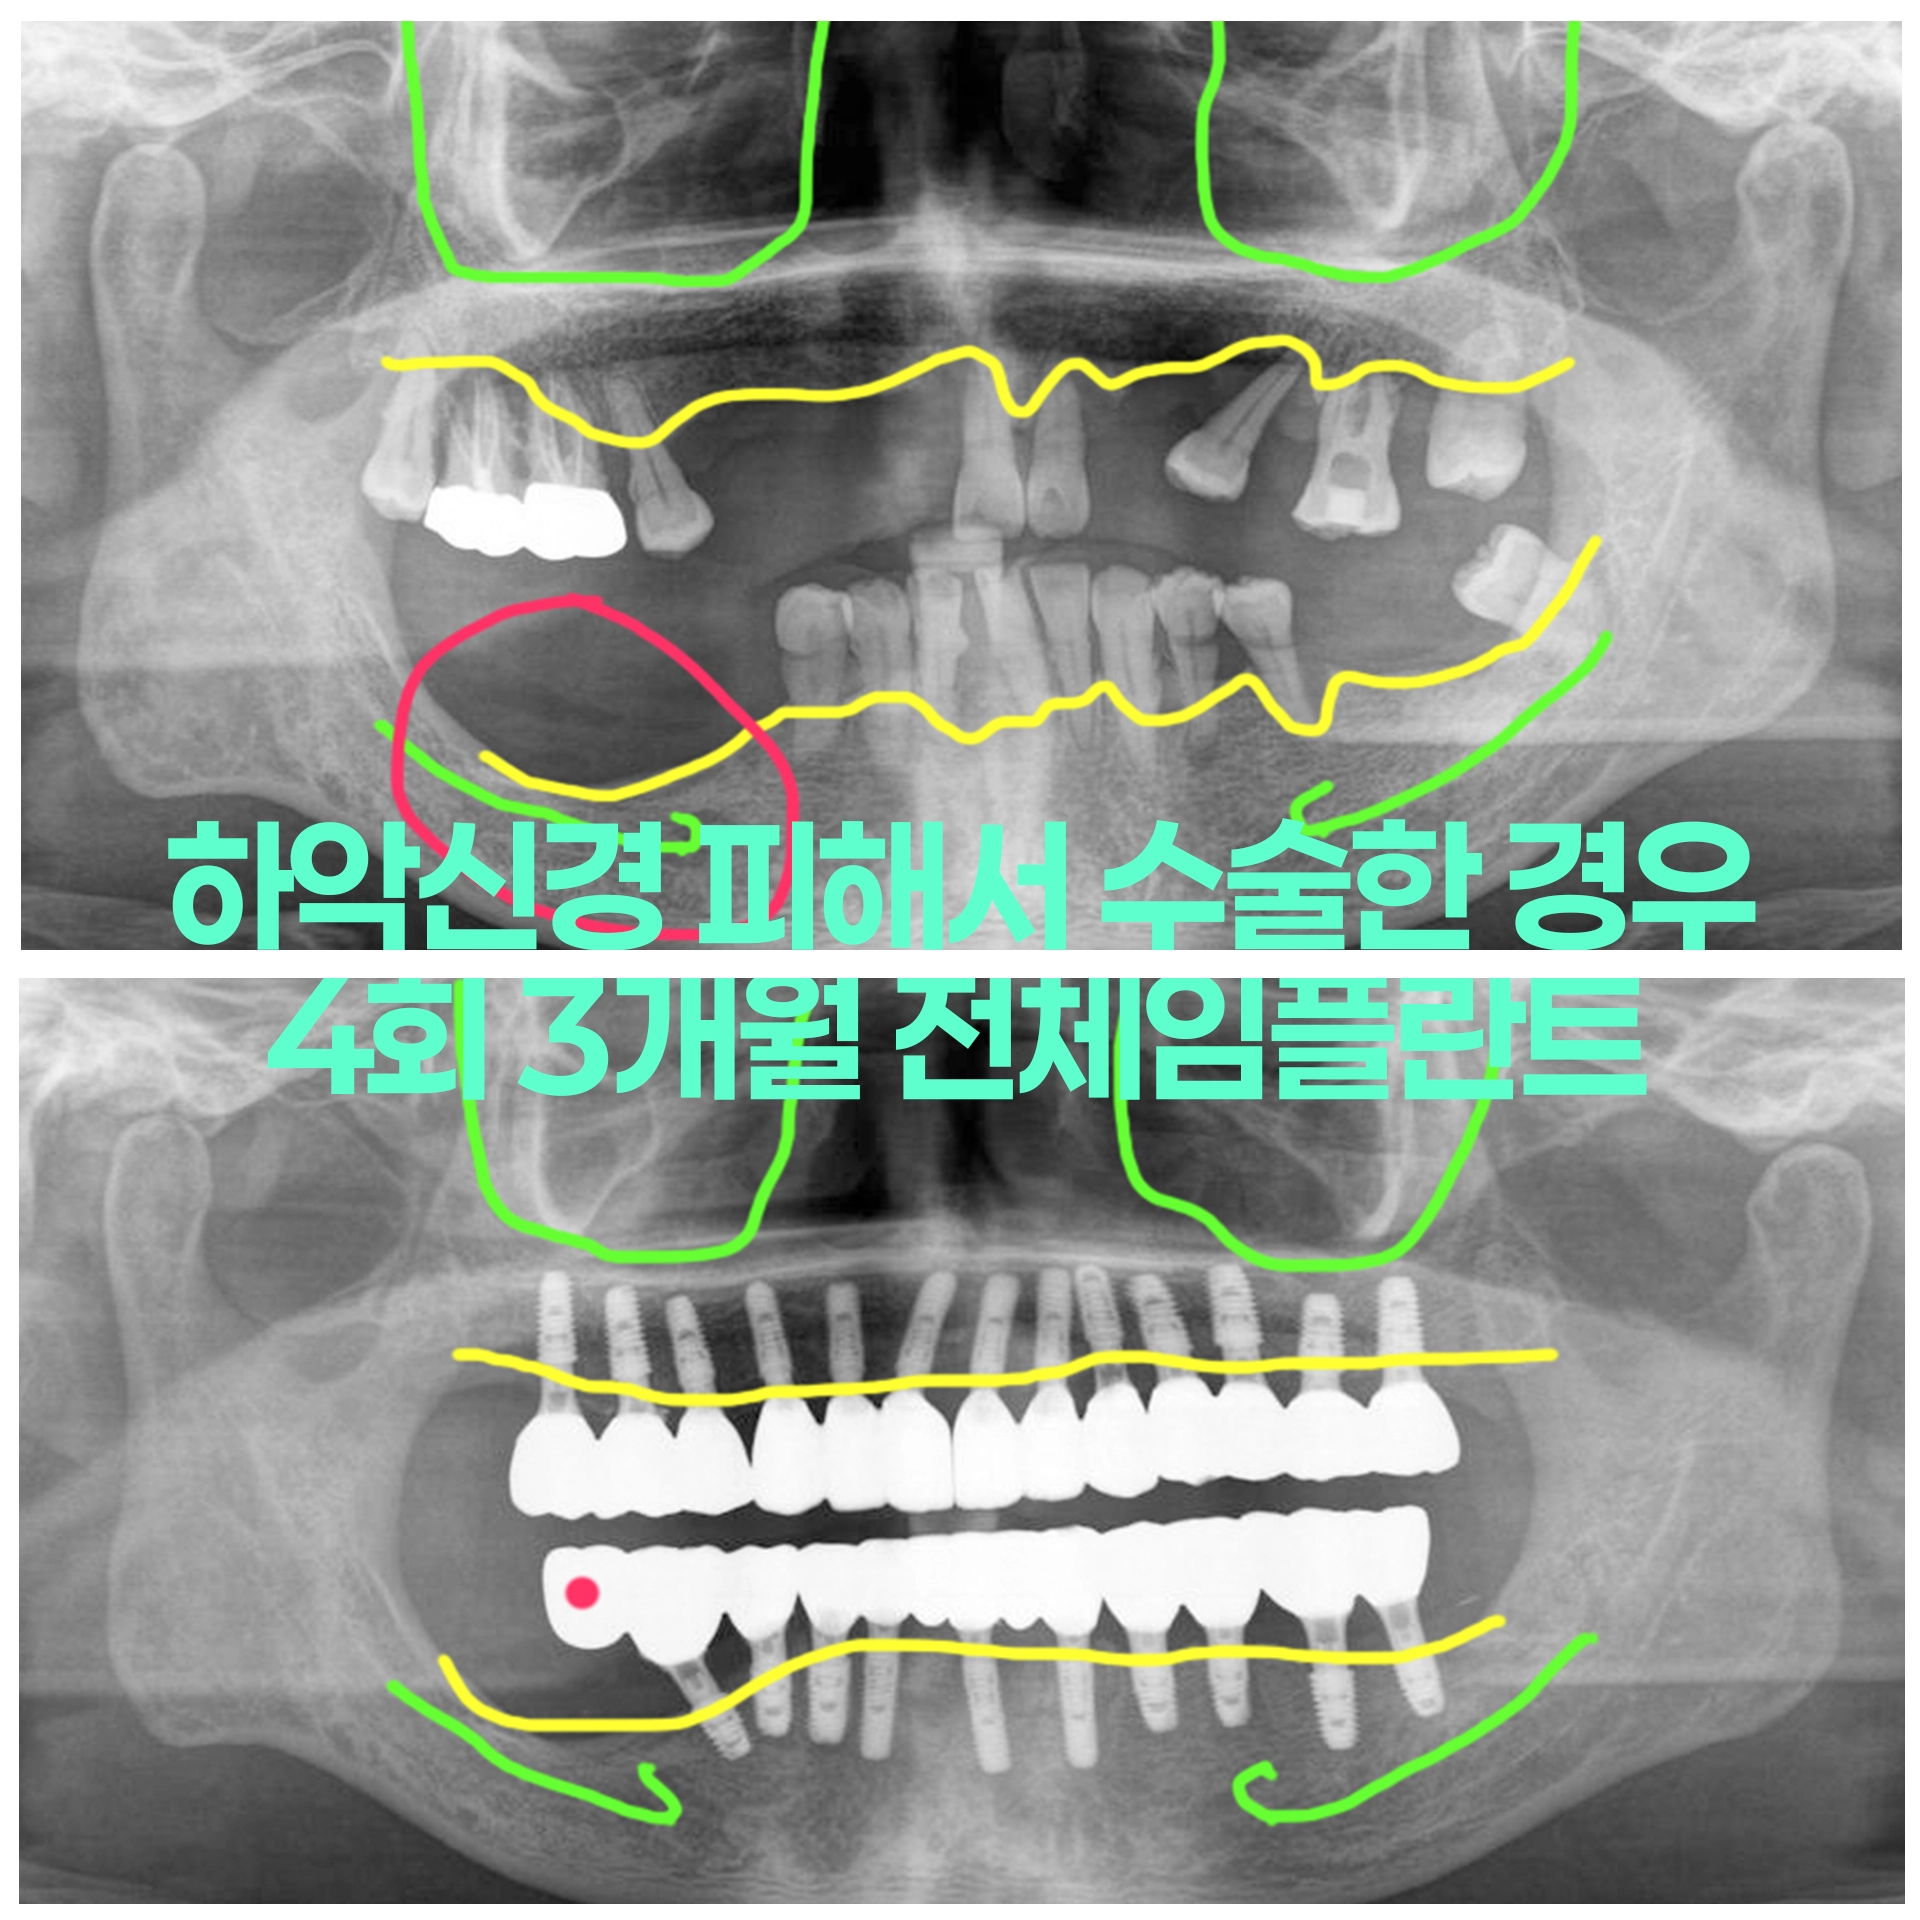

70대 남성 위아래 틀니 하악신경 주의 건강한 치아 남기고 즉시하중 임시치아 전체임플란트